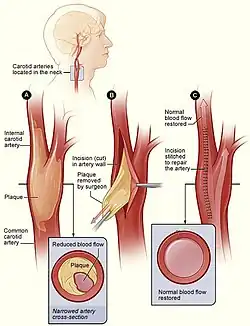

Cerebrovascular disease

Vascular surgeons are responsible for treating extracranial cerebrovascular disease as well as the interpretation of non-invasive vascular imaging relating to extracranial and intracranial circulation such as carotid ultrasonography and transcranial doppler. The most common of cerebrovascular conditions treated by vascular surgeons is carotid artery stenosis which is a narrowing of the carotid arteries and may be either clinically symptomatic or asymptomatic (silent). Carotid artery stenosis is caused by atherosclerosis whereby the buildup of atheromatous plaque inside the artery causes narrowing.

Symptoms of carotid artery stenosis can include transient ischemic attack or stroke. Both symptomatic and asymptomatic carotid stenosis can be diagnosed with the aid of carotid duplex ultrasound which allows for the estimation of severity of narrowing as well as characterize the plaque. Treatment can include medical therapy, carotid endarterectomy or carotid stenting.

The Society for Vascular Surgery publishes clinical practice guidelines for the management of extracranial cerebrovascular disease.[19] Less common diseases involving cerebral circulation treated by vascular surgeons include vertebrobasilar insufficiency, subclavian steal syndrome, carotid artery dissection, vertebral artery dissection, carotid body tumor and carotid artery aneurysm among others.